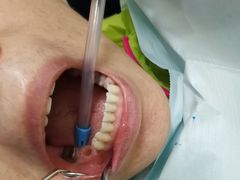

• 爱贝口腔·牙周诊疗·种植修复中心

• -爱贝口腔·牙周诊疗·种植修复中心

君祥云华域君酒 | 23-11-04